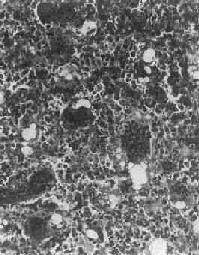

镜下,骨肉由明显间变的梭形或多边形肉细胞组成,细胞大小不等,核形奇异,大而深染,核仁明显,易见病理性核分裂像。肿细胞直接形成肿性类骨组织或骨组织,是诊断骨肉的最重要的组织学依据。所形成的类骨组织或骨组织在不同肿或同一肿的不同部位多少不等。往往可看到肿性骨质发生过程中各阶段的形态,最早期在恶性肿细胞间出现均质红染的胶原样物质,其后红染物质逐渐增多,将肿细胞分隔疏远,构成小梁或片状的肿性类骨组织(图17-8)。类骨组织可伴钙盐沉着,其内的肿细胞固缩变小,形成肿性骨质。骨肉内也可出现肿性软骨(图17-9)。

图17-8 骨肉

多形性肉细胞直接形成肿性骨样组织